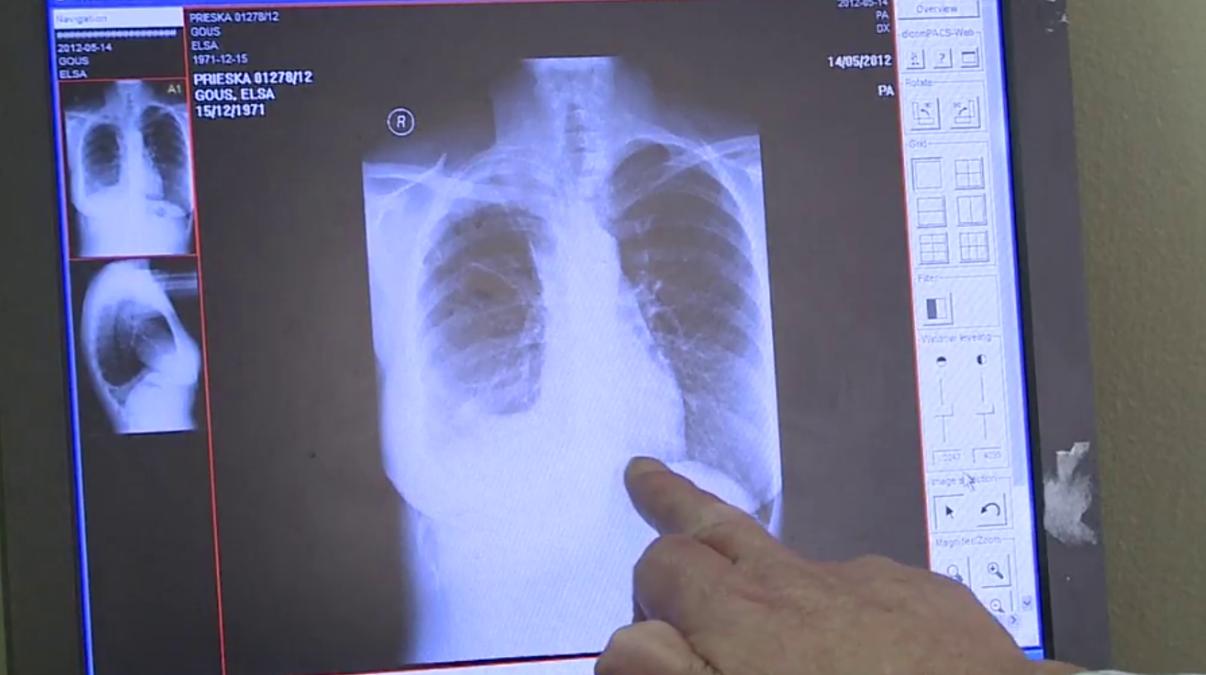

而这种肉眼根本无法看见的东西会随着空气一道从人的口鼻进入体内的呼吸系统。石棉纤维虽会被人体的免疫细胞识别并吞噬,酶却无法分解从而致使整个免疫细胞死亡,此时酶就会随石棉纤维一同溢出至细胞外,并开始肆意破坏肺部其他正常的细胞运作进程,引发诸如石棉肺、间皮瘤等恶性疾病。

甚至长期暴露在有石棉纤维存在的空气中,还有患上间皮癌甚至是肺癌的风险,癌症有多恐怖想必不用我再度强调,这就足以看出农村石棉瓦的危害性有多大了。

据流行病学的数据表明,全球患有恶性胸膜间皮瘤的患者有近八成人都有过直接或间接的石棉暴露史。